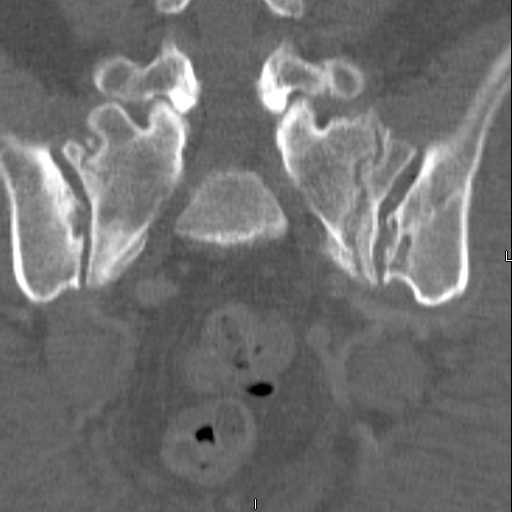

Here are a recent patient’s example slides...

54 yo Female Fell c/o Pain

3 Months After Fall

Continued Pain & Immobility

(+) Instability to Compressive Manual Exam

Pelvic CT Scan - 3 Months After Fall

Sacral Injuries

Ramus Fractures